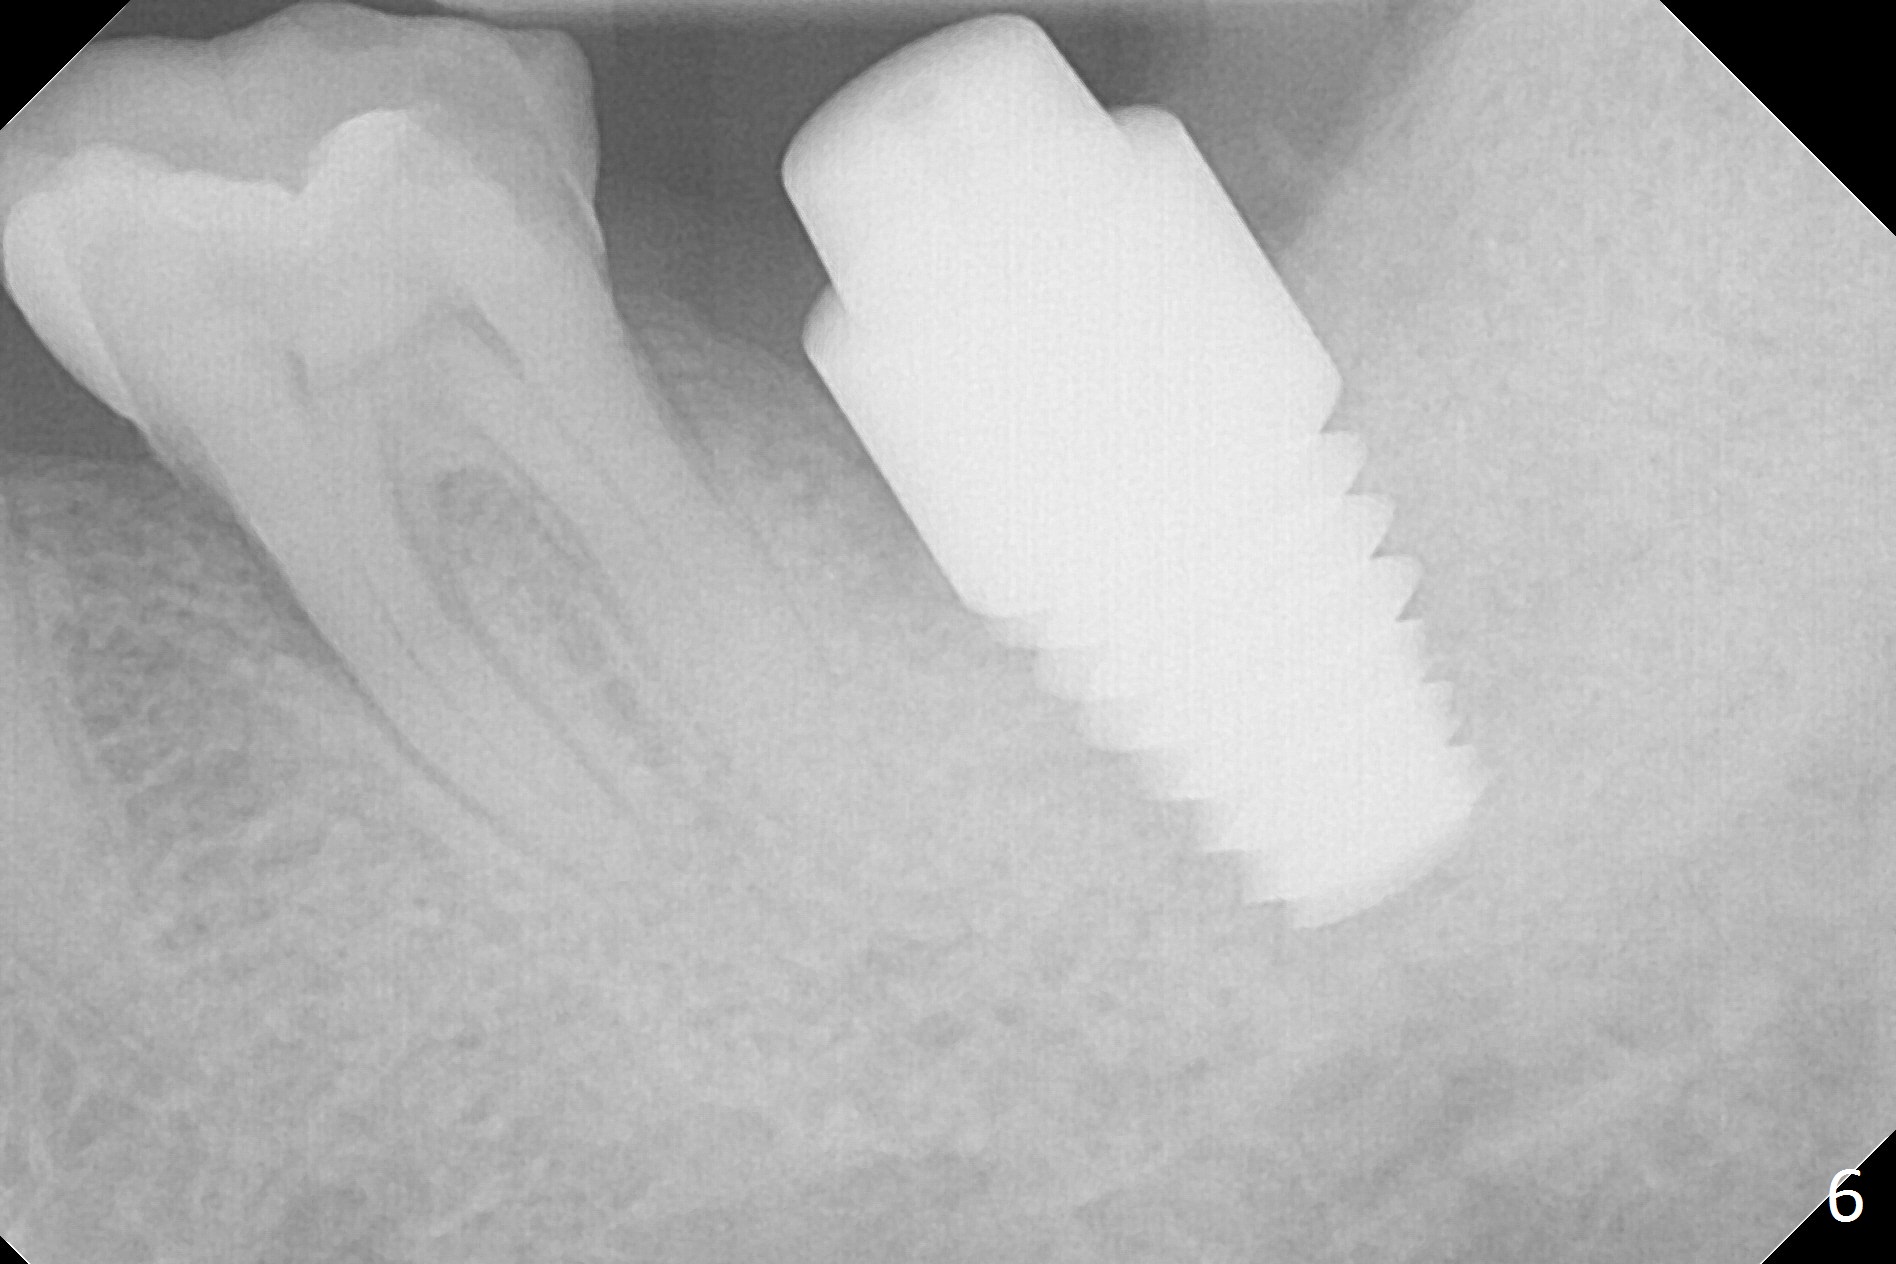

It appears that the patient chews on the left postop, since the provisional perforates with loose abutment nearly 3 months postop and the tooth #3 has occlusal sensitive chip. The implants seems to have osteointegrated (Fig.6). To improve oral hygiene, the provisional is not recemented. The patient will return for impression in 2 weeks. It appears that there is short healing time for large implant. There is no bone loss 7 months post cementation (Fig.7). The buccal gingiva is lightly erythematous without tenderness 1 year 7.5 months post cementaion. Water pik is being used, although chronic periodontitis is not under control. Retrospectively, surgery should be shifted to socket preservation when a moderate implant (5 or 5.5 mm) fails to achieve primary stability. The extra large implant (8 mm for example) leaves a little gap buccolingually. Guided surgery would allow precise placement of the moderate implant without change in trajectory. The crown becomes loose because of occlusal perforation and limited vertical space. When a new crown is cemented, the bone density around the coronal threads is high (Fig.8 *). While the bone remains stable at #4 (6 months post RCT), 13 (4 years 6 months post cementation) and 18 (2 years 5 months post cementation), there is severe bone loss at #2 and 31 (Fig.9).